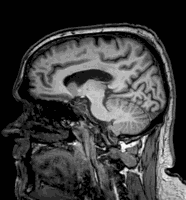

He knew something was wrong when he suffered a seizure in 2022.

He thought his headaches were from needing new glasses.